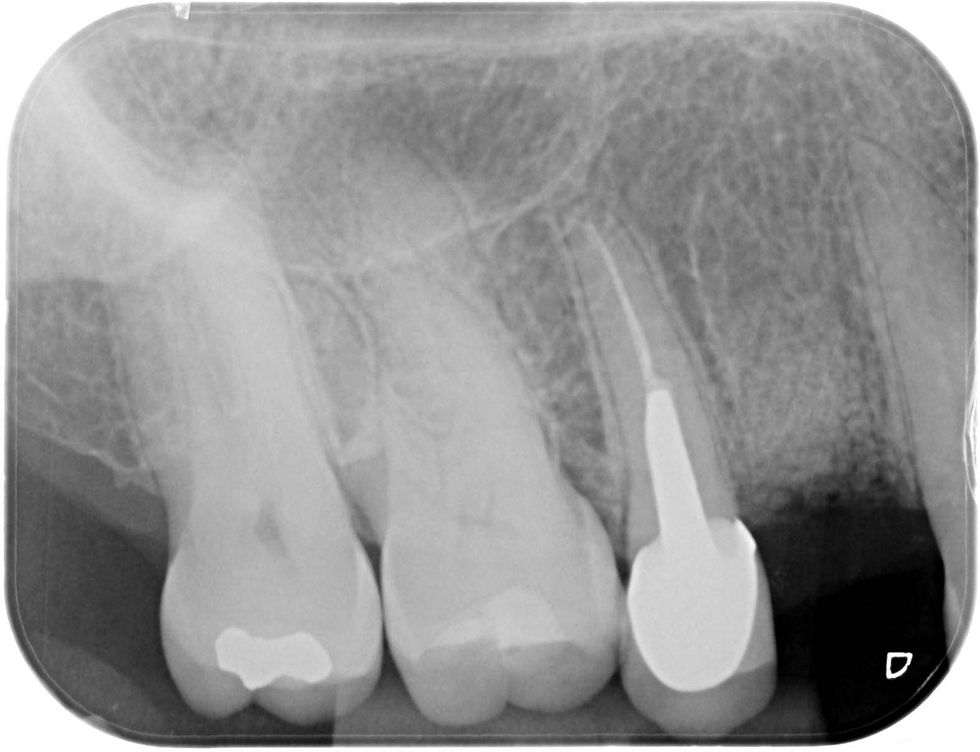

Pre-operative intraoral radiograph of the element 1.4.